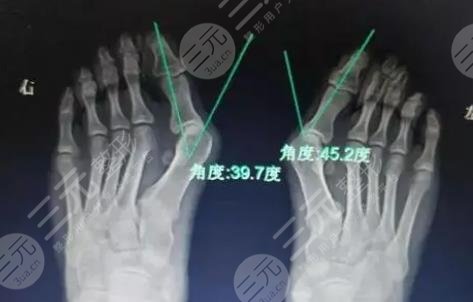

2、手術緩解

手術緩解是針對于,已經(jīng)沒有辦法采用物理方式矯正的大腳骨外翻患者,主要的實施方式。如果我們再通過了鞋子的調整和使用一些用具沒有明X果之后,并且已經(jīng)對于日常的生活產(chǎn)生了影響,就可以采用手術的方法來緩解,能夠有的改良腳部畸形狀態(tài)。

緩解大腳骨外翻的方式比較多,具體選擇哪一種方法需要根據(jù)每個人的病情去評估。在選擇方式之前,要根據(jù)患者的癥狀,通過身體的檢查和X線來綜合去判斷,不可以盲目的去選擇,因此一定要到正規(guī)的醫(yī)院,請經(jīng)驗豐富的醫(yī)生去幫助選擇和緩解。在緩解之后也要定期進行康復訓練,避免一些不良反應出現(xiàn)。